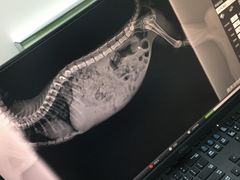

• 嘉美宠物医院

• -嘉美宠物医院